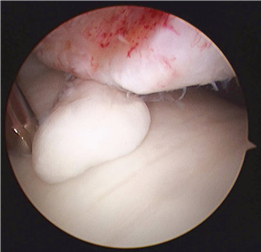

Clinical & Radiographic Imaging Archive

Clinical Image